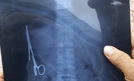

Wietnamscy chirurdzy wyjęli z żołądka mężczyzny 15-centymetrowe nożyczki, które miał w brzuchu od czasu operacji przeprowadzonej 18 lat wcześniej. Pacjent przez lata funkcjonował bez problemów. Mieszkający niedaleko Hanoi mężczyzna w 1998 roku po wypadku...